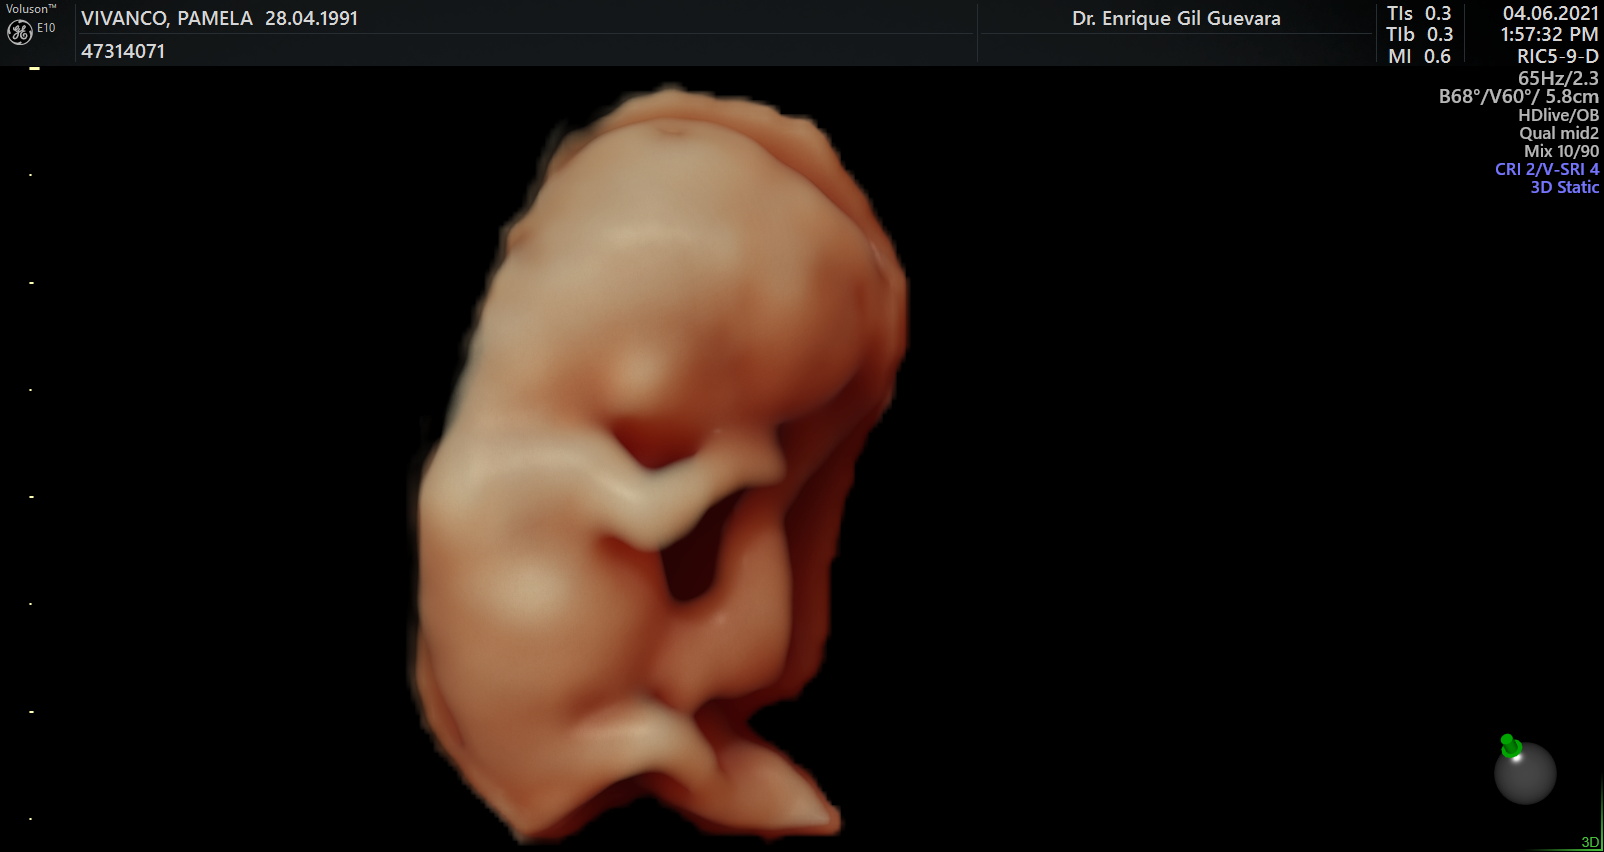

Somos expertos en detección temprana de anomalías. Brindamos una gama completa de Ultrasonidos Fetales y Ecografías 5D-7D: